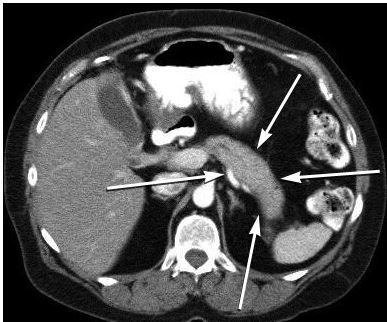

CT finding of the pancreas in autoimmune pancreatitis

“Sausage-shaped” pancreas